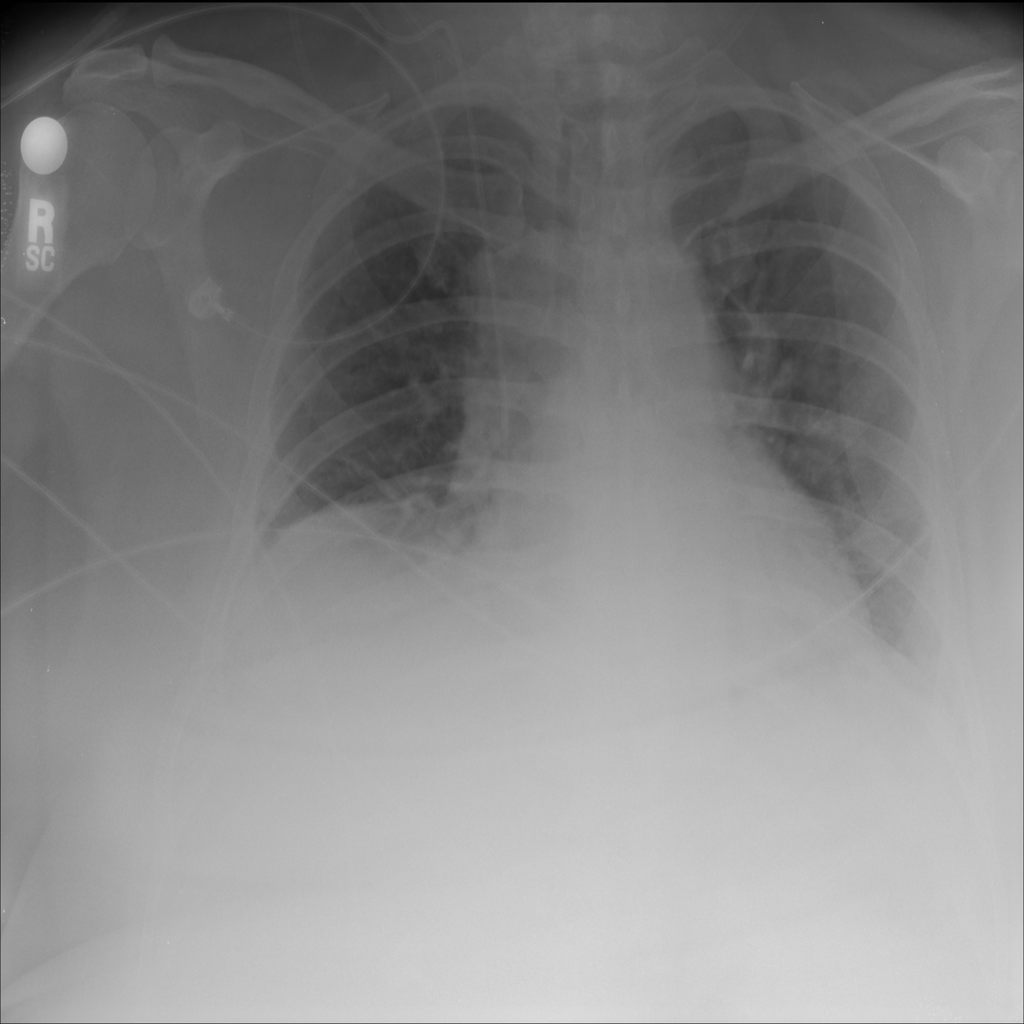

PAT-299B · IMG-003Atelectasis

PAT-299B · IMG-003

AP